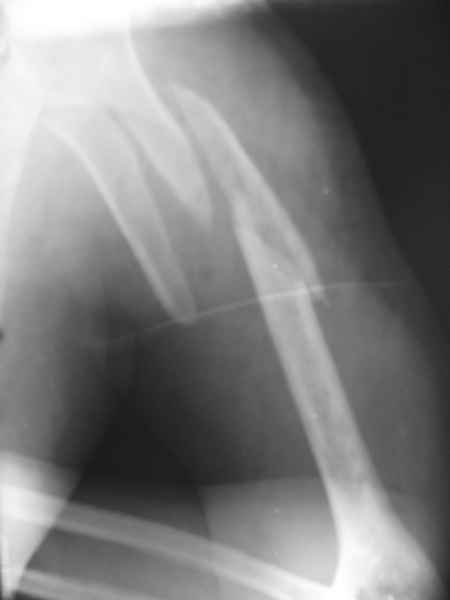

Александр А. 01 Июль 2010, 00:29

Добрый вечер!

Приложение как пример.

Что иллюстрирует этот пример? Это была множественная травма? Если это был изолированный перелом, то "золотой стандарт" - консервативное лечение.

Консервативно он уже лечился до этой операции в течение трёх с половиной месяцев.

А именно такой вариант операции выбран из экономических соображений.

вообще, торчашие в субакромиальное пространство шипы оставляют неизгладимое впечатление. Не думаю, что таким имплантом есть смысл гордиться

Снимок с имплантом из металла с памятью формы получился "sexy", но нарушены все каноны остеосинтеза. Потому что при комбинации двух ущербных систем одновременно повреждается внутри канальное и наружное кровообращение.

Кроме интрамедуллярного остеосинтеза, имеются другие варианты фиксации, наружный фиксатор и например здесь перелом плеча с повреждением нерва леченный открытым методом. Применен задний доступ с инспекцией нерва, межфрагментарная компрессия, фиксация узкой пластиной 4.5 мм.